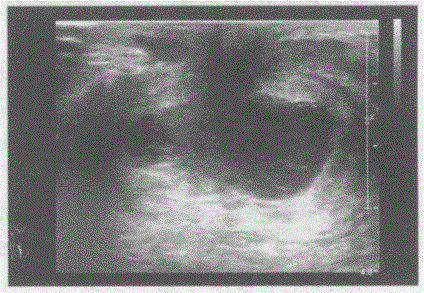

问题 临床资料:女,29岁,哺乳期,自述右乳房肿痛1周。 临床物理检查:右乳房红、肿、热、痛,体温38.5℃。 超声综合描述:右乳头后方可见低回声区,形态不规则,边界显示不清,内可见不规则无回声区,无回声区内可见中强回声光点浮动,探头加压局部疼痛明显,CDFI:周边可见散在点状动静脉血流信号。见下图及彩图。 {图1} 超声提示:

选项 A.乳腺癌 B.急性乳腺炎合并乳腺脓肿 C.乳腺导管扩张 D.乳腺囊肿

答案 B